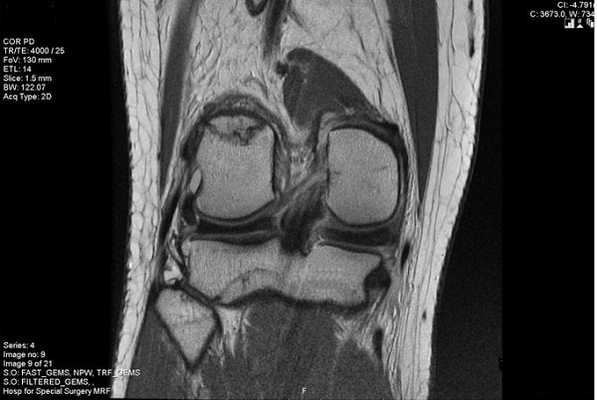

МРТ коленного сустава. Т2-взвешенная МРТ в сагиттальной плоскости. Полный горизонтальный разрыв заднего рога медиального мениска (стрелка).

Разрывы могут быть полные или частичные, что определяется по МРТ коленного сустава.

МРТ коленного сустава также может определить форму разрыва, например вертикальный горизонтальный разрыв может быть в виде «ручки»: симптом отсутствия «бабочки» - нет центральной части мениска. Вертикальные разрывы также при МРТ коленного сустава могут быть радиальными и косыми (“клюв попугая”).